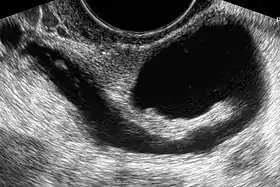

| Left hydrosalpinx on gynecologic ultrasonography | |

Hydrosalpinx may be diagnosed using ultrasonography as the fluid filled elongated and distended tubes display their typical echolucent pattern. However, a small hydrosalpinx may be missed by sonography. During an infertility work-up a hysterosalpingogram, an X-ray procedure that uses a contrast agent to image the fallopian tubes, shows the retort-like shape of the distended tubes and the absence of spillage of the dye into the peritoneum. If, however, there is a tubal occlusion at the utero-tubal junction, a hydrosalpinx may go undetected. When a hydrosalpinx is detected by a hysterosalpingogram it is prudent to administer antibiotics to reduce the risk of reactivation of an inflammatory process.